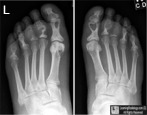

Indian Journal of Radiology Shah D M, Patel S B, Shah S R, Goswami K G. Mesenteric panniculitis a case Plain radiography provides very few findings. PubMed journal article Radiology-pathology conference: neutrophilic fasciitis and panniculitis of the feet (Sweet. s syndrome was found in Unbound MEDLINE.

Radiology-pathology conference: neutrophilic fasciitis and

Radiology–pathology conference: neutrophilic fasciitis and. MRI findings for parotid lupus Radiology Case Reports.